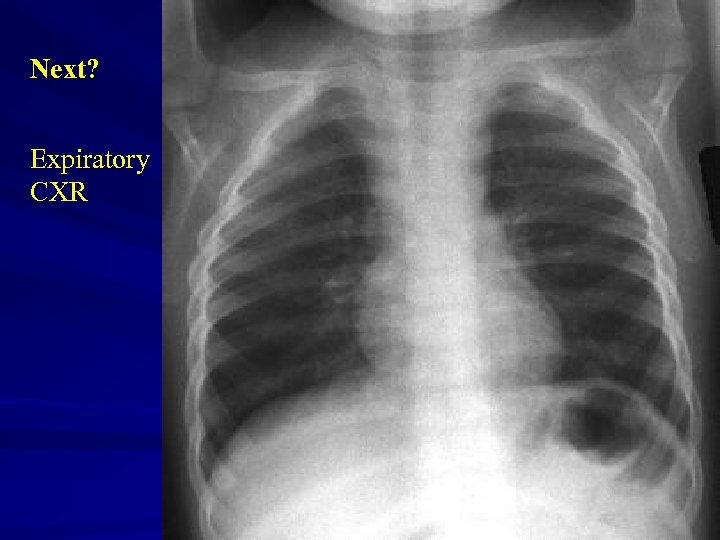

Next? Expiratory CXR

Inspiratory View Expiratory View

Right Decub View

Investigations Xrays Ø Lateral neck Ø Chest – inspiratory, expiratory, decubitus views Expiratory views Overinflation (partial obstruction with inspiratory flow) Volume loss with mediastinal shift towards obstructed side (partial obstruction with expiratory flow) Atelectasis (complete obstruction)

Decubitus views Normal Smaller volumes and elevated diaphragm on side down Abnormal Hyperinflation or “normal” volumes in decub position If suspected … Need a bronchoscope to rule out or remove Foreign Body